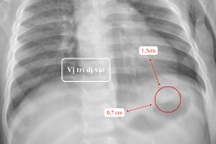

Kết quả chụp X-quang, các bác sĩ phát hiện một đồng xu có kích thước 3-4cm trong dạ dày của bệnh nhi.